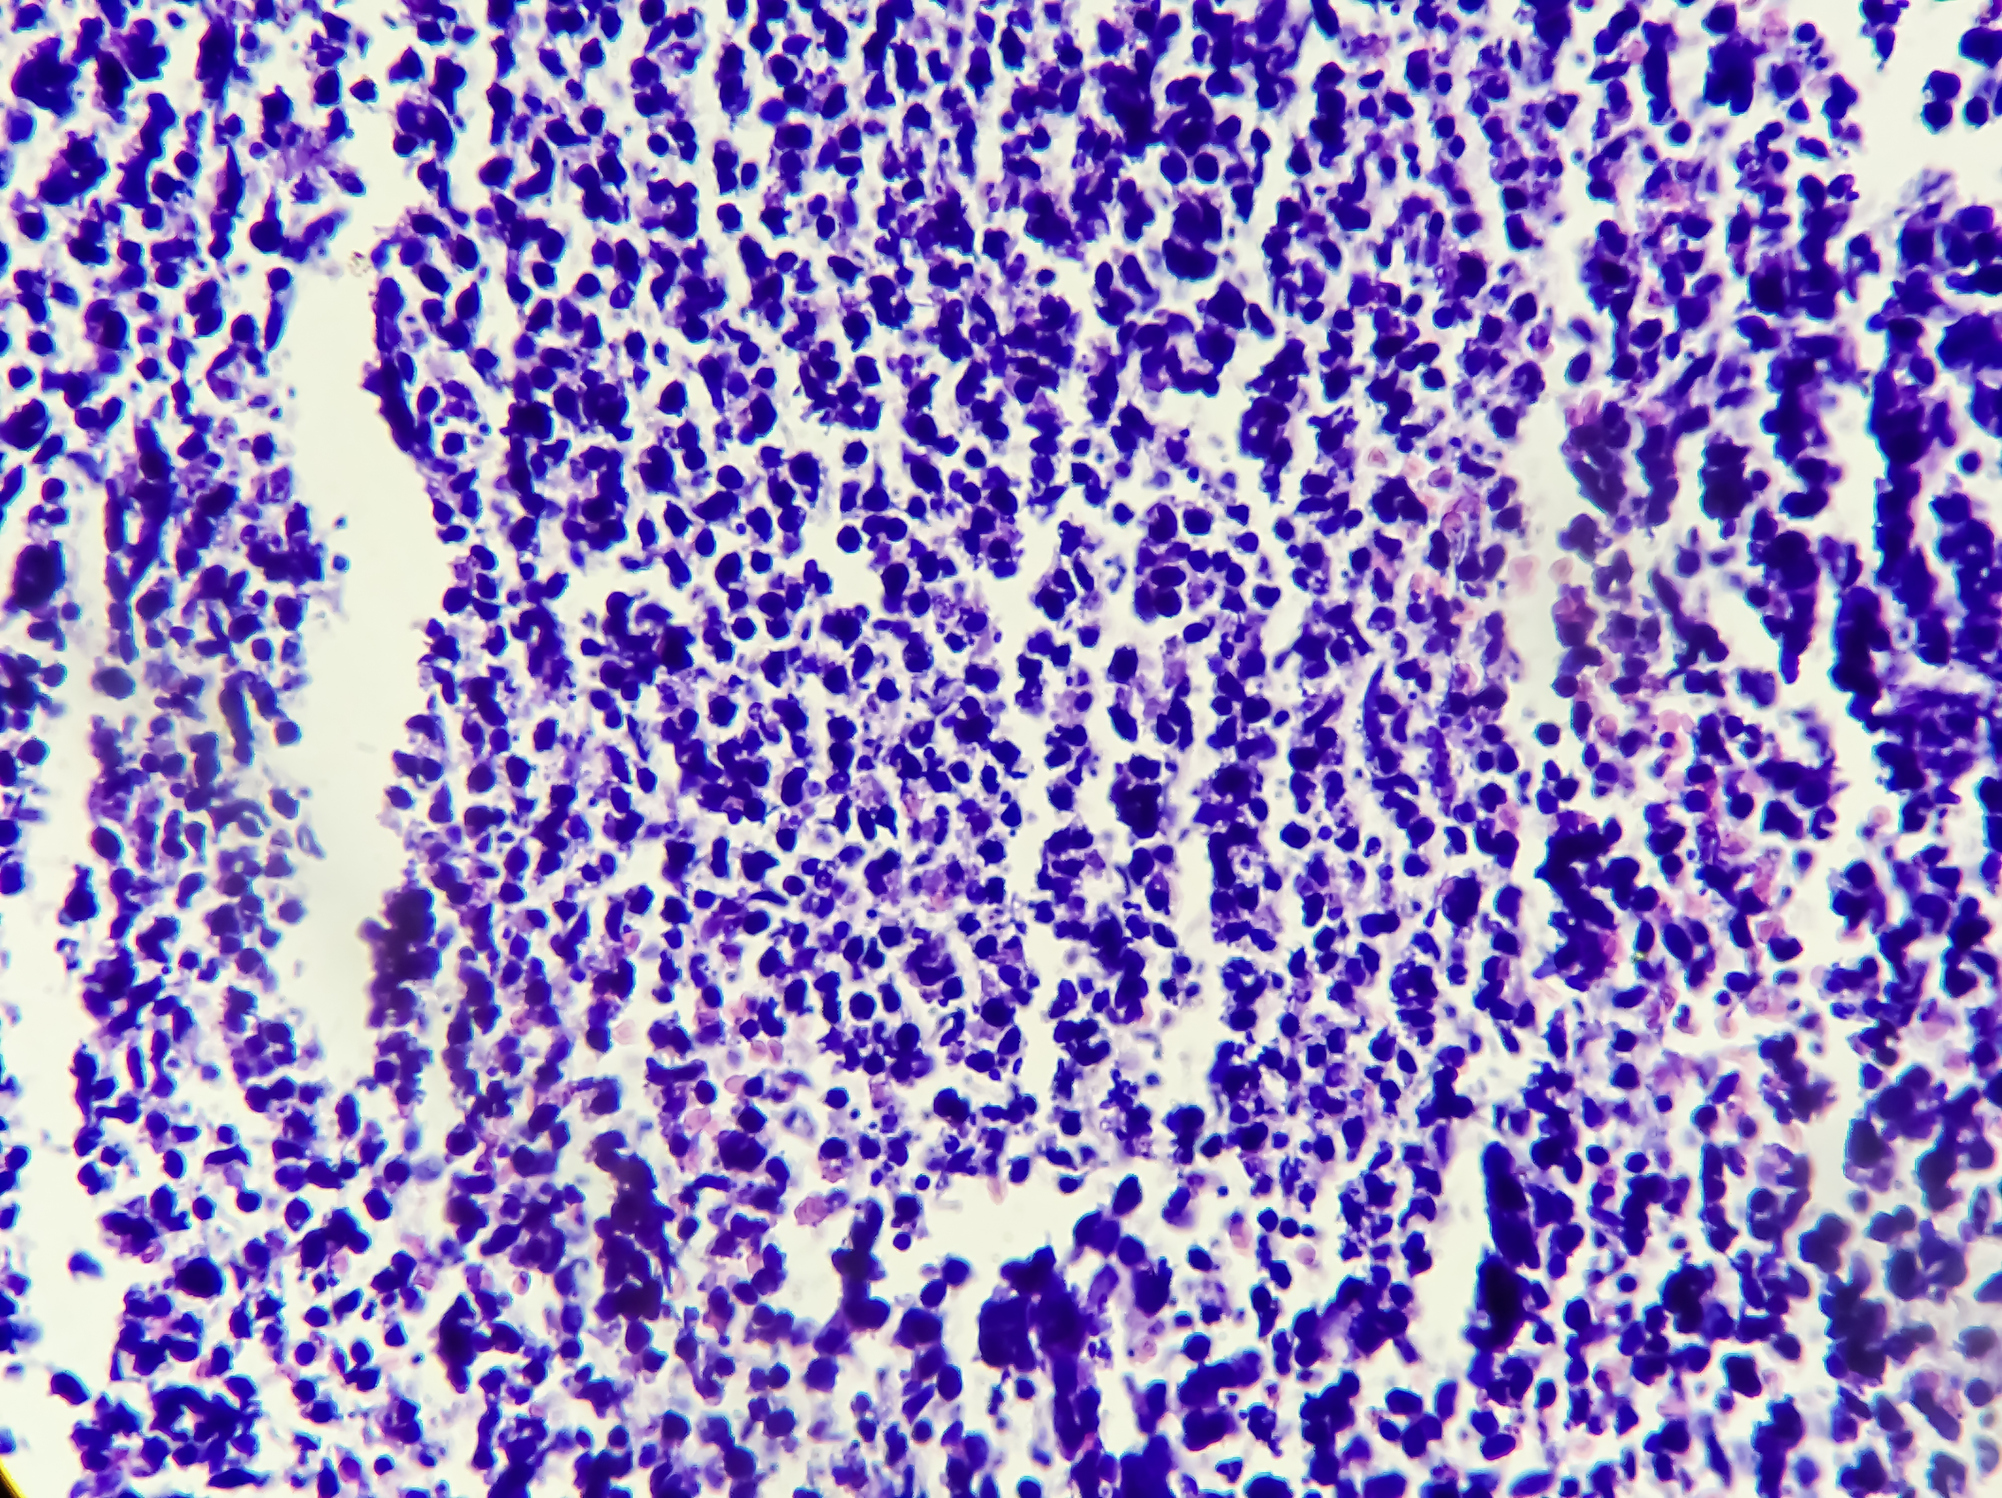

該男大學生姓陳,住台中市,他只有21歲,十分年輕、平時作息正常,且無不良嗜好,未料於某日因腎臟發炎發高燒而住院,經醫生安排電腦斷層檢查,意外發現他的左腎有一顆2.2厘米的惡性腫瘤,因此住院做觀察與治療。進一步做磁振造影檢視後,陳同學的腫瘤報告顯示,他確實罹患第一期的腎臟細胞癌。

孫宏舜醫生指出,目前腎臟細胞癌的成因不明,臨床症狀變化多端,有些甚至沒有症狀,患者多半都是在無意中發現罹癌。

腎臟細胞癌常見症狀包括貧血、發燒、惡病質、虛弱、體重減輕等,出現這些警訊時就該特別注意。孫宏舜說,其中最常見的三個典型症狀是「血尿」、「腹部腫塊」,以及「腰部痠痛」,這三類症狀同時出現的機率約10~15%,但通常此時癌症已轉移至其他部位了。